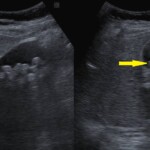

・腹部エコー検査にて胆のうや肝臓、腎臓、膵臓の検査を行います。

*胆石